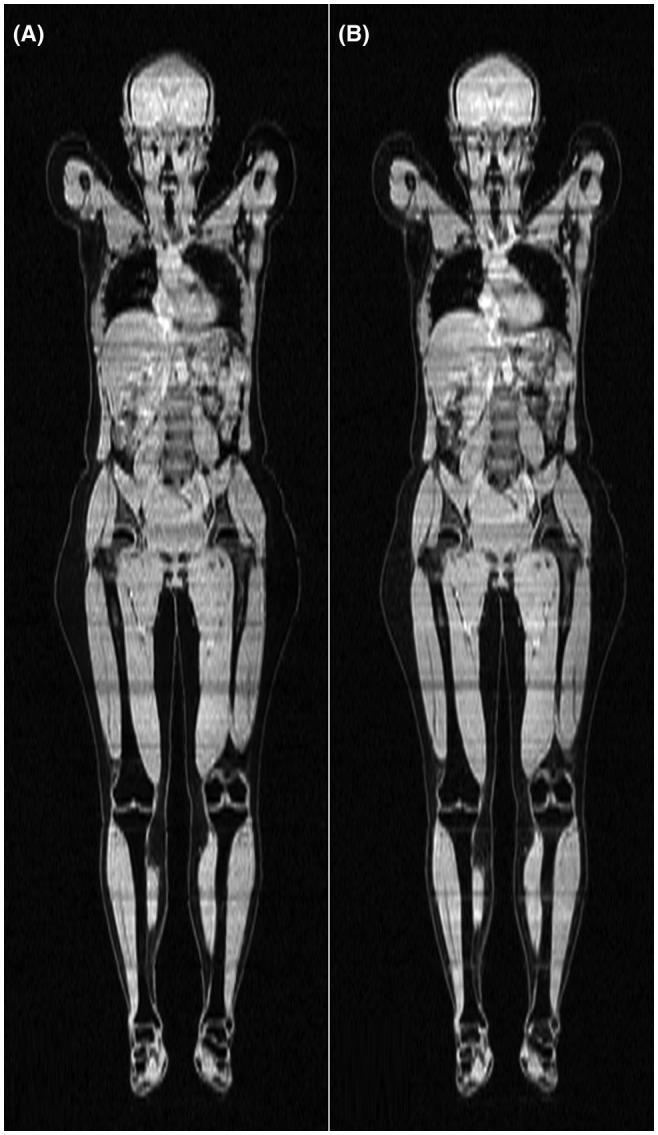

使用卷积神经网络分离全身梯度回波扫描中的水脂信号。

Separation of water and fat signal in whole-body gradient echo scans using convolutional neural networks.

To perform and evaluate water-fat signal separation of whole-body gradient echo scans using convolutional neural networks.

Whole-body gradient echo scans of 240 subjects, each consisting of 5 bipolar echoes, were used. Reference fat fraction maps were created using a conventional method. Convolutional neural networks, more specifically 2D U-nets, were trained using 5-fold cross-validation with 1 or several echoes as input, using the squared difference between the output and the reference fat fraction maps as the loss function. The outputs of the networks were assessed by the loss function, measured liver fat fractions, and visually. Training was performed using a graphics processing unit (GPU). Inference was performed using the GPU as well as a central processing unit (CPU).

RESULTS

The loss curves indicated convergence, and the final loss of the validation data decreased when using more echoes as input. The liver fat fractions could be estimated using only 1 echo, but results were improved by use of more echoes. Visual assessment found the quality of the outputs of the networks to be similar to the reference even when using only 1 echo, with slight improvements when using more echoes. Training a network took at most 28.6 h. Inference time of a whole-body scan took at most 3.7 s using the GPU and 5.8 min using the CPU.

CONCLUSION

It is possible to perform water-fat signal separation of whole-body gradient echo scans using convolutional neural networks. Separation was possible using only 1 echo, although using more echoes improved the results.